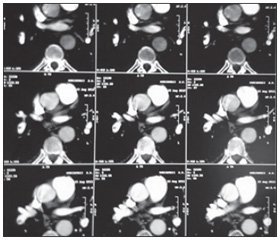

После проведения тотальной селективной церебральной ангиографии была выявлена мешотчатая аневризма передней мозговой, передней соединительной артерии с дивертикулами, передняя трифуркация слева, признаки церебрального ангиоспазма (рис. 1). Пациенту запланировано оперативное вмешательство — краниотомия, клипирование мешотчатой аневризмы в условиях общего обезболивания. На момент проведения операции состояние пациента было тяжелое стабильное, I стадия по Ханту — Хессу, очаговой неврологической симптоматики не было, цефалгия была не выражена. После индукции в наркоз (тотальная внутривенная анестезия + искусственная вентиляция легких) и обработки кожи произведен разрез, наложено 6 фрезевых отверстий и сделано три пропила кости. Через 1 ч 5 мин с момента начала операции у пациента внезапно развилась остановка кровообращения по механизму фибрилляции желудочков. Немедленно начаты реанимационные мероприятия. Появление выраженного цианоза кожных покровов головы, шеи и плечевого пояса указывало на возможную причину остановки кровообращения — развитие ТЭЛА. При проведении комплекса СЛР сохранялась рефрактерная фибрилляция желудочков в ответ на электрическую дефибрилляцию и введение амиодарона (300 мг после 3-го неэффективного разряда и 150 мг после 4-го неэффективного разряда дефибриллятора). Учитывая разрыв мешотчатой артериальной аневризмы, проведение тромболизиса было абсолютно противопоказано. На 40-й минуте СЛР после нанесения 12-го разряда дефибриллятора получено восстановление синусового ритма на кардиомониторе, а затем и самостоятельного кровообращения. Пациент переведен в ОРИТ, гемодинамика удерживалась введением вазопрессоров (мезатон 0,05 мкг/кг/мин), проводилась респираторная поддержка. При лабораторном исследовании на D-димер в раннем постреанимационном периоде получен результат 9,32 мкг/мл (норма — до 0,5 мкг/мл). Через 6 часов с момента восстановления самостоятельного кровообращения пациент понимал обращенную речь и выполнял элементарные команды. На следующие сутки была проведена спиральная компьютерная томография легких с контрастированием, в результате в нижнедолевой ветви легочной артерии справа обнаружен тромб 5 мм в диаметре и длиной около 4 см (рис. 2).